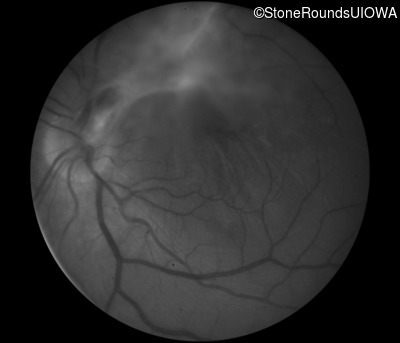

Visit at age: 33 years

Fundus Photography - Left - 20/200 sc

Exemplar